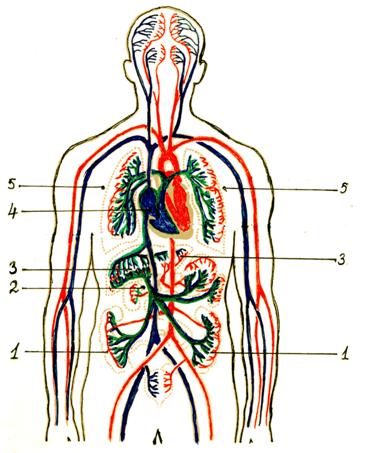

Кровеносная система человека: структура и функции